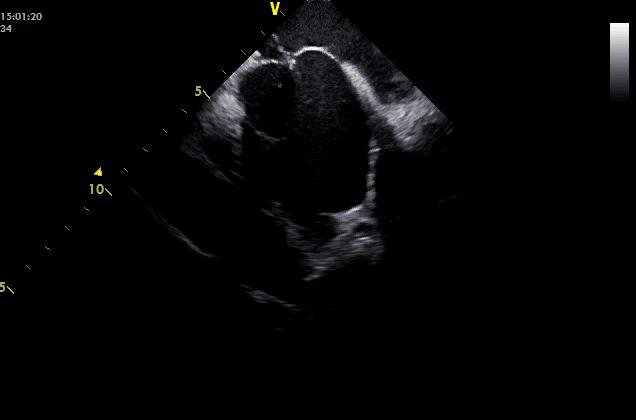

第1例患者,男性,61岁。发现室性早搏5年,动态心电图提示24小时室早总数35000+次,口服药物效果不佳,需要行射频消融术治疗。但该患者心电图表现提示为乳头肌起源室性早搏,由于乳头肌本身结构复杂,毗邻组织较多,常规的三维电解剖标测系统不能充分显示乳头肌结构,而且射频导管也很难准确到位和稳定贴靠,所以该区域的室早射频消融难度较高,普通的三维标测射频消融术费时费力,成功率低,复发率高。使用心腔内超声技术(ICE)可以帮助介入医生更加直观地看到乳头肌位置,还可以更加精确地定位消融导管的位置,实时显示导管贴靠的情况,显著提高了手术的成功率,同时有效减少X线的用量,减轻辐射对病人和医生的伤害。